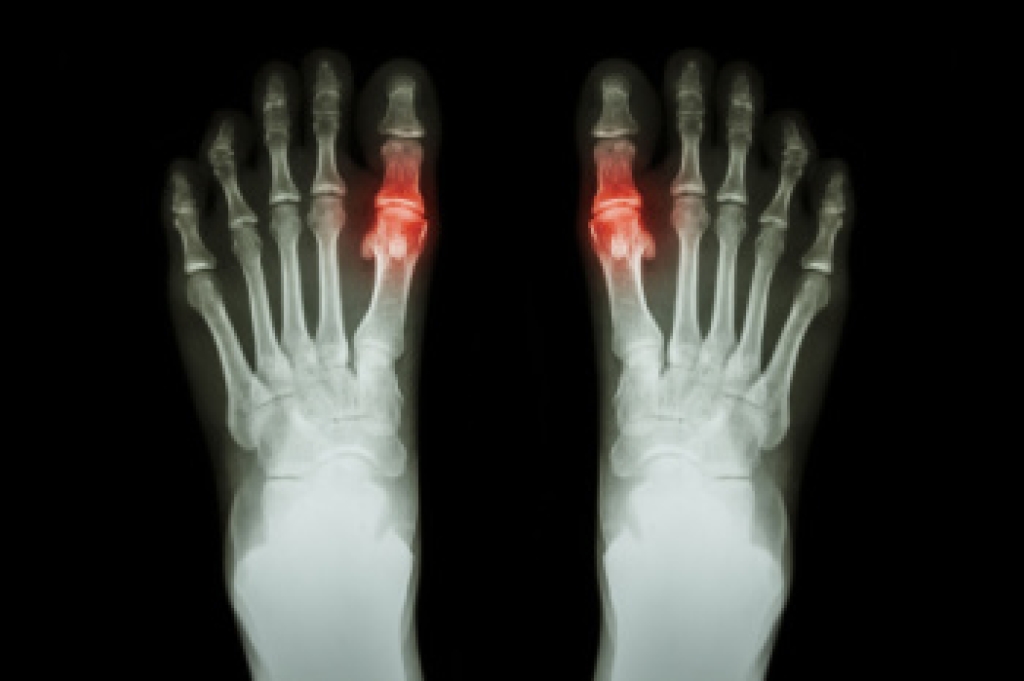

Arthritis, particularly osteoarthritis, is a common cause of foot pain and discomfort. Osteoarthritis is a degenerative joint disease that causes the cartilage in the joints to break down, leading to pain, stiffness, and swelling. In the feet, it can affect areas like the toes, ankles, and the arch. Common symptoms include joint tenderness, limited movement, swelling, and difficulty walking. The causes of osteoarthritis in the foot can range from age and genetics to previous injuries or repetitive stress. Over time, the wear and tear on the cartilage causes painful friction between bones. If you are experiencing foot pain or stiffness, a podiatrist can offer effective treatments. This type of doctor can recommend custom orthotics, pain management options, targeted exercises, or surgical procedures if needed. Seeking expert care early can help manage symptoms and improve mobility. If you are suffering from painful arthritis, it is suggested that you schedule an appointment with a podiatrist to get the relief you need.

Arthritis is a term that is commonly used to describe joint pain. The condition itself can occur to anyone of any age, race, or gender, and there are over 100 types of it. Nevertheless, arthritis is more commonly found in women compared to men, and it is also more prevalent in those who are overweight. The causes of arthritis vary depending on which type of arthritis you have. Osteoarthritis for example, is often caused by injury, while rheumatoid arthritis is caused by a misdirected immune system.

Arthritic symptoms range in severity, and they may come and go. Some symptoms stay the same for several years but could potentially get worse with time. Severe cases of arthritis can prevent its sufferers from performing daily activities and make walking difficult.